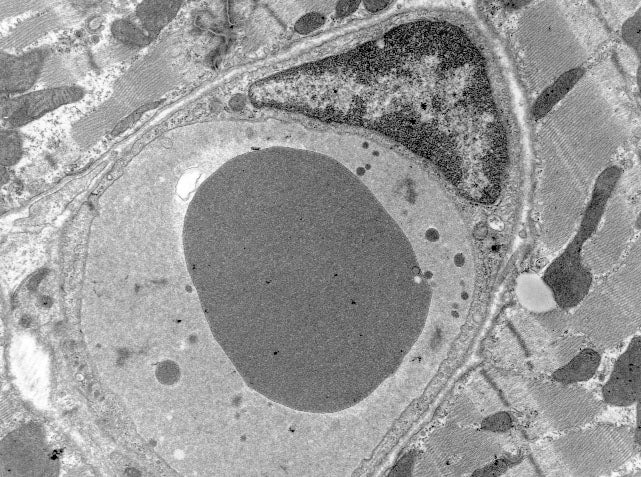

TEMBF